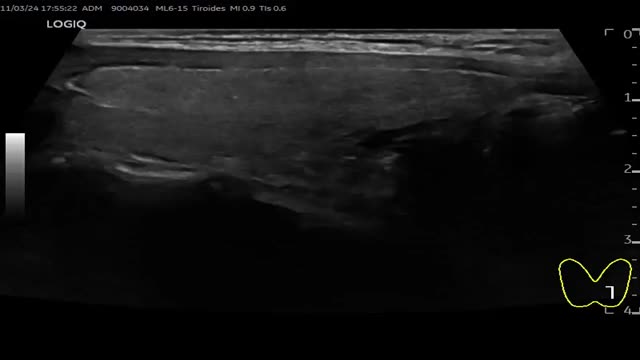

≥7 puntos: TIRADS 5 (probabilidad de malignizar >20%). Clasifica el nódulo como altamente sospechoso. Se realizará seguimiento si el nódulo es ≥5mm y PAAF si el nódulo es ≥10mm (fig. 6 y video 5)

Figura 6.TI-RADS 5 A: Nódulo sólido hipoecoico, mal delimitado, de márgenes mal definidos, con morfología «más alto que ancho» y con microcalcificaciones. B: Nódulo sólido muy hipoecoico, de márgenes bien definidos, con microcalcificaciones, que se agrupan en el borde inferior del nódulo y dejan algo de sombra posterior.